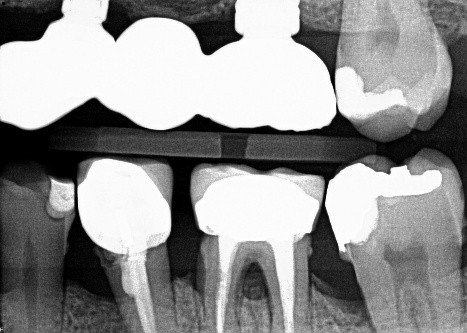

7 / 50

7. (Select ONE OR MORE correct answers)

The radiograph shows evidence of

8 / 50

8. (Select ONE OR MORE correct answers)